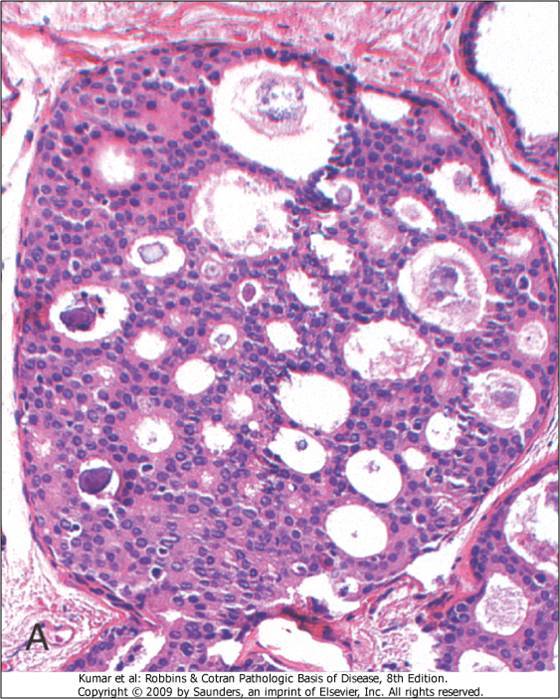

What is the morphology of mammary duct ectasia?

Tons of lipid-laden macrophages and cholesterol deposits. Granulomatous inflammation surrounds the cholesterol deposits.